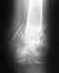

17 лет назад получила травму:оскольчатый перелом обеих бедренных костей.На одной ноге прелом был открытый, из-за чего развился остеомиелит.

Лечение получила только одно-лежала на вытяжении. В итоге оба перелома срослись неправильно,под углом во внешнюю сторону. ноги сейчас "колесом". Хожу без костылей, палочки.Последнее время болят колени. Можно ли исправить "кривизну" и каким образом это делается? И чем грозит такая деформация если ее не исправить?